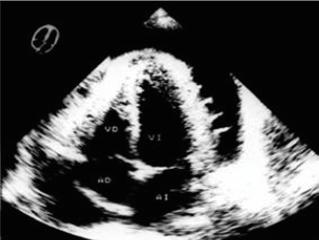

La combinación de hipertrofia de ventrículo izquierdo con agrandamiento de la aurícula derecha es muy sugestiva de esta miocardiopatía.

Se pueden observar ondas T profundamente invertidas (“ondas T negativas gigantes”) en las derivaciones precordiales. Presencia de arritmias ventriculares.

Ecocardiograma:

Aumento inexplicable de un espesor de la pared del ventrículo izquierdo ≥ 15 mm.

En las formas obstructivas, se observa el movimiento anterior sistólico (SAM) de la válvula mitral.